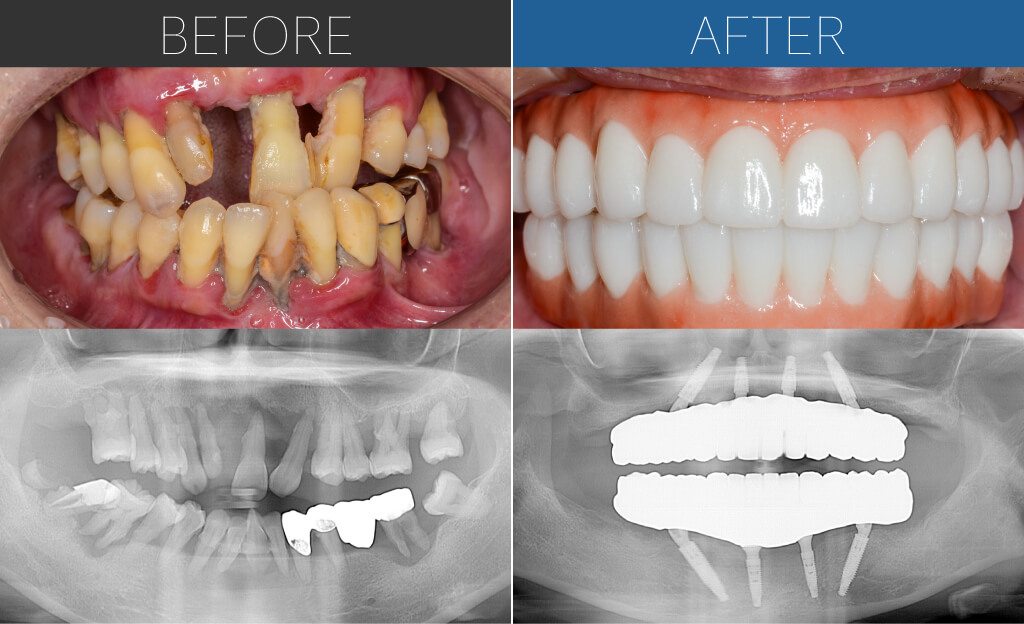

– Upper:All-on-4 Quad Zygoma + Pterygoid implants

– Lower:All-on-4

Age:60s

| 主訴 | 3年前に入れ歯作ったが残っていた歯が抜けて使えなくなった。上の歯もグラグラしており抜けてきそう。入れ歯は安定剤をガッツリつけていないとすぐに落ちてしまい、話しづらいし食べづらい。 |

| 治療内容 | 上顎は全体的に重度の骨吸収のため、4本のザイゴマインプラントによるクワッドザイゴマに加え、両側にテリゴイドインプラントを併用。下顎は基本的な4本埋入によるオールオン4。上下ともに即時荷重により手術当日に仮歯を固定。 |